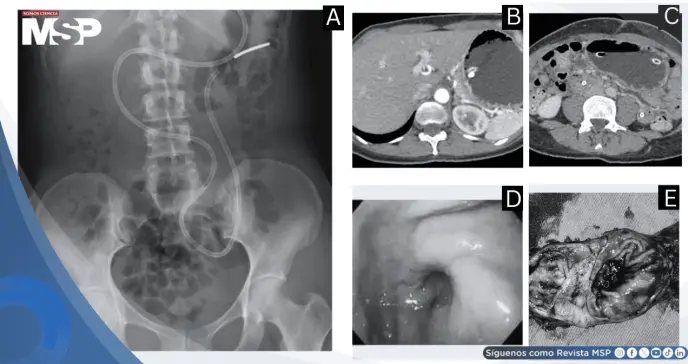

La evaluación inicial mediante radiografía simple de abdomen evidenció abundante materia fecal sin signos francos de obstrucción intestinal.

Sin embargo, la persistencia y severidad de los síntomas motivaron la realización de tomografía computarizada abdominal contrastada, que reveló hallazgos preocupantes: marcada dilatación de la cámara gástrica con transición abrupta a nivel de la región pilórica y colapso de las asas intestinales distales, configurando un patrón característico de obstrucción de la salida gástrica.

Ante la sospecha de estenosis pilórica con alta probabilidad de etiología maligna, se procedió a realizar endoscopia digestiva alta con toma de biopsias de la región pilórica.

Los hallazgos endoscópicos revelaron un píloro excéntrico con engrosamiento mucoso y estenosis secundaria, observándose edema y pérdida del patrón mucoso normal, características sugestivas de proceso infiltrativo.

A nivel del antro y píloro se identificó una masa submucosa de aproximadamente 2 centímetros de longitud con compromiso circunferencial significativo, respetando la capa mucosa, hallazgo que se confirmó al examinar la pieza quirúrgica.

El análisis histopatológico exhaustivo de la pieza quirúrgica estableció el diagnóstico definitivo de adenomioma gástrico. El examen microscópico reveló la arquitectura característica de esta entidad: estructuras ductales y glandulares benignas revestidas por epitelio columnar, entremezcladas con fascículos de músculo liso, todo ello localizado en la capa submucosa con extensión hacia la muscular propia, sin evidencia de atipia celular ni características de malignidad.